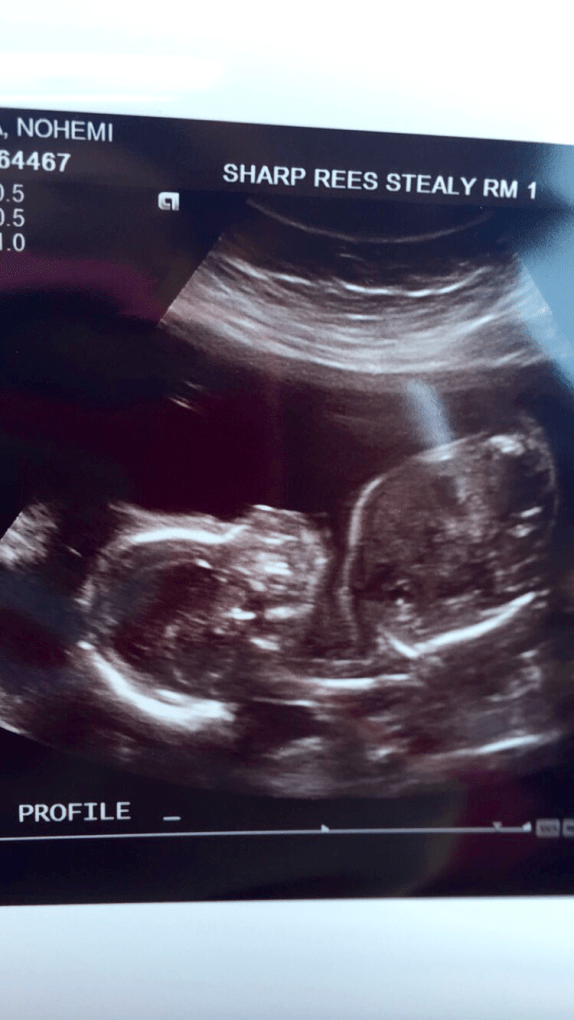

Well I’ve reached my due date (October 21) and still no baby boy. The anticipation makes this wait feel like torture but hopefully baby boy decides to make his appearance soon, as we are all anxiously waiting to meet him.

I am currently at 40 weeks and so ready to pop. I started dilating at 38 weeks but haven’t had any contractions so the waiting game continues. After my 41 week appointment we will schedule induction, hopefully the next day! Hopefully labor starts before that on its own but there is comfort in knowing that soon we will get to meet baby boy. We are very excited to bring him home and prepared to shower him with lots of love.